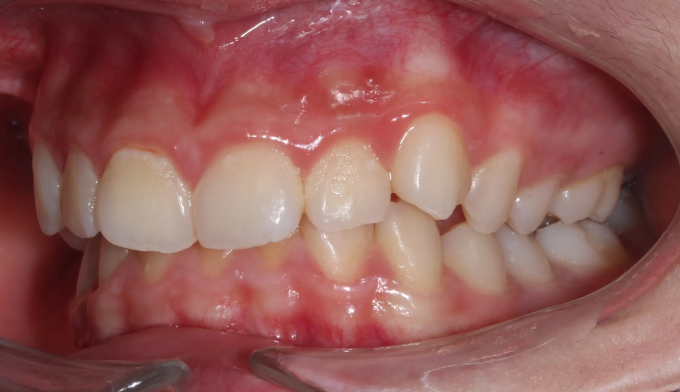

위 작은어금니가 겹쳐져서 맹출하였습니다.

공간이 부족하므로 먼저 양쪽으로 치아를 벌려 공간을 확보해준 후 겹쳐진 치아들을 배열해줍니다.

치아 배열 중 앞니가 뻐드러지지 않게 조심합니다.

총 치료기간은 20개월입니다.